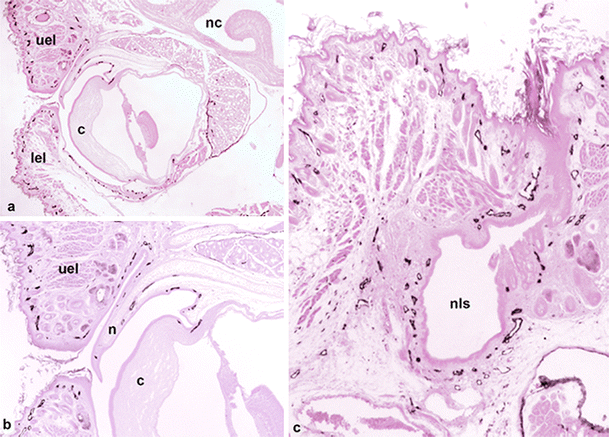

In the eye, Schlemm’s canal has previously been identified as a lymphatic-like vessel (Aspelund et al. 2014; Kizhatil et al. 2014; D.-Y. Park et al. 2014; Ramos et al. 2007). Our staining shows that a Lyve-1-positive vessel is present in the limbus of the cornea and seems to be part of a lymphatic network of the conjunctiva, which also covers the murine nictitating membrane (Fig. 5a, b). Additionally, the eyelids contain a dense network of initial lymphatics. At the medial angle of the eye, these lymphatics form a continuum with the lymphatic networks accompanying the NLD towards the inferior nasal turbinate (Fig. 5c). Moreover, squamous epithelial cells, which appear to be homologous to the Tenon capsule of the human eye, are Lyve-1-positive.

Lyve-1-positive lymphatics of the eye. a Overview showing the eye with the cornea (c), upper eyelid (uel) and lower eyelid (lel) and nasal cavity (nc). Magnification ×20. Bar 400 μm. b Higher magnification of a. Of note is the lymphatic network starting at the limbus of the cornea (c) and extending from the conjunctiva of the nicitating membrane (n) into the upper eyelid (uel). Magnification ×40. Bar 200 μm. c Medial angle of the eye and the nasolacrimal sac (nls), which discharges into the NLD and has a dense network of lymphatics. Magnification ×40. Bar 200 μm